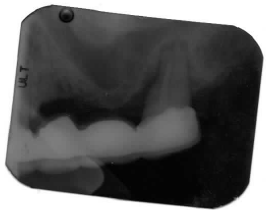

因为条件实在太差(见附上的牙片),且病人71岁了。故问一下:1)能不能做?2)如能做,怎么做,分几步?

金杭晴,看了你的病例,我认为是可以手术的。因为你提供的病情不多,我个人意见,首先在#12牙远中处切断牙桥,拔除#15牙。等3个月后,拍个CT片,准备植牙手术。如果病人牙列完好,可在#13,15植牙,因为这两处骨质厚度不够,所以要Sinus lift 和植骨同时一起做。半年后再安牙桥。如果,#18牙缺失,可只做#13,14牙植入,#13牙 sinus lift 可选经牙槽嵴植牙处进入,或者与#14牙一起,经上颌窦外侧开窗进入,lift和植骨,植牙一起完成,至少六𠆤月后安牙冠,最好将这俩𠆤牙冠连作一体。仅供参考。小沐